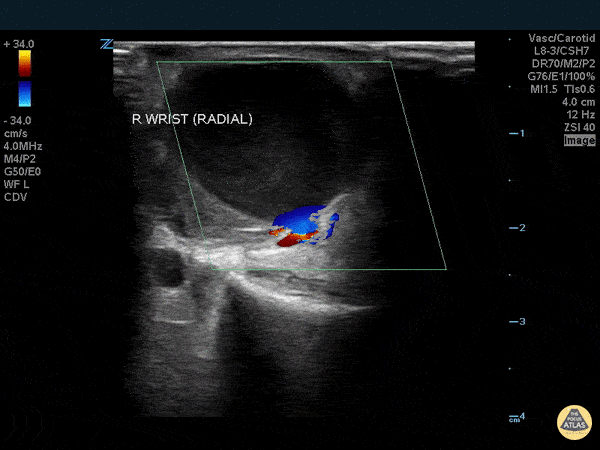

Vascular - Pseudoaneurysm - Radial Artery

WCUME 2017 Submission and WINNER of "Best POCUS" Category Radial artery pseudoaneurysm 5 days following transradial coronary angiography. Thrill. Instant diagnosis with POCUS. Stephen Alerhand, MD - Mount Sinai Hospital